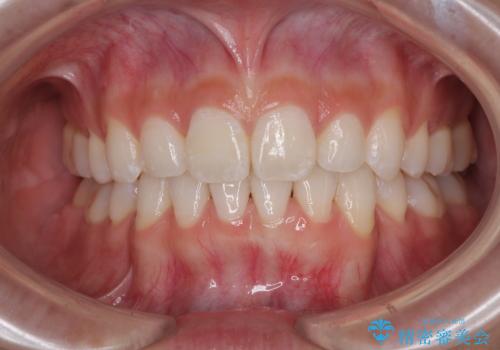

下唇に前歯が当たって跡が残ってしまう状態でしたが、スッキリとした口元に仕上げることができました。

斜め前に飛び出した前歯 抜歯矯正で素敵な横顔に